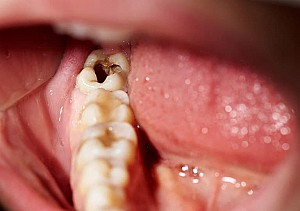

- Lợi trùm hay đã cắt lợi trùm nhưng tái phát. Lợi trùm phủ lên một phần mặt nhai của răng dẫn đến dắt các mảnh thức ăn và là nơi sinh sôi cho vi khuẩn dẫn đến sưng đau kéo dài, mức độ càng ngày càng trầm trọng.

- Mọc thẳng nhưng có tình trạng dắt thức ăn dẫn đến tình trạng hôi miệng, chảy máu khi đánh răng hay tự nhiên và viêm lợi khư trú, lâu dần tiến triển thành viêm nha chu (gây lung lay răng), sâu kẽ răng…

- Không thể vệ sinh tốt ở vùng răng khôn do nhiều nguyên nhân: gây buồn nôn do kích thích họng,…dẫn đến tình trạng sâu răng, bám đọng nhiều cao răng và viêm lợi.